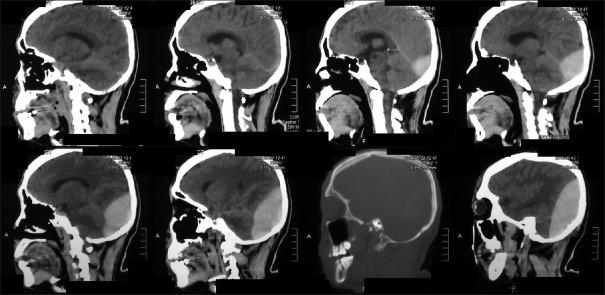

Traumatic supra- and infra-tentorial extradural hematoma (TSIEDH) is a rare lesion constituting <2% of all extradural hematomas. There are only a few published articles about TSIEDH. This study included three patients with TSIEDH who were treated and operated at Dr. Soetomo General Hospital, Surabaya, Indonesia, from August 2015 to July 2016. Two patients sustained injuries in traffic accidents and one patient was injured by fall. The male to female ratio was 1:2. Glasgow Coma Scale (GCS) score ≤8 was present in one and GCS score of 9-12 was present in two patients. The brain computed tomography scan verified linear fracture of occipital bone in one and linear fracture of occipital bone with lambdoid suture separation in two patients. Early diagnosis and early surgical intervention of TSIEDH are imperative because the deterioration of TSIEDH is sudden and quick. We presented our experience in treating patients with TSIEDH in Dr. Soetomo General Hospital, Surabaya, Indonesia.

创伤性幕上和幕下硬膜外血肿(TSIEDH)是一种罕见的病变,占所有硬膜外血肿的比例不到2%。关于TSIEDH的已发表文章很少。本研究纳入了2015年8月至2016年7月在印度尼西亚泗水苏托莫综合医院接受治疗和手术的3例TSIEDH患者。2例患者在交通事故中受伤,1例患者因跌倒受伤。男女比例为1:2。1例患者格拉斯哥昏迷量表(GCS)评分≤8,2例患者GCS评分为9 - 12。脑部计算机断层扫描显示1例患者枕骨线性骨折,2例患者枕骨线性骨折伴人字缝分离。由于TSIEDH的恶化突然且迅速,因此对其进行早期诊断和早期手术干预至关重要。我们介绍了在印度尼西亚泗水苏托莫综合医院治疗TSIEDH患者的经验。